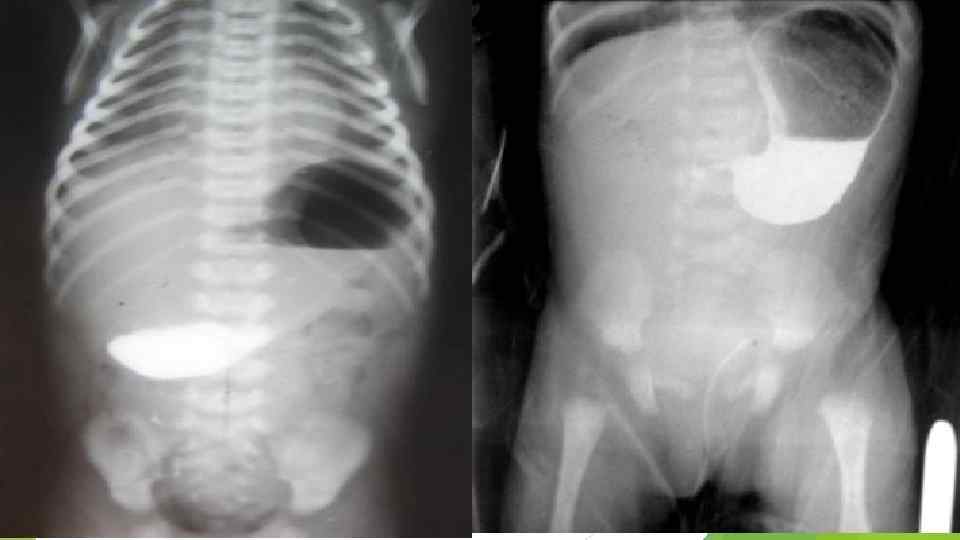

Пилоростенозды анықтау әдістері. Пилоростенозды анықтауда R-графиялық зерттеудің маңызы зор. Баланы тік тұрғызып құрсақ қуысына шолу Rграфиясын жасағанда, асқазанның созылғаны және онда ауаның көп мөлшерде жиналғаны байқалады.

Тиімді тәсіл асқазанға рентген контрастты ерітінділер жіберіп тексеру. Левин тәсілі. Ол үшін асқазанға түтікше арқылы жылытылған 10% глюкоза ерітіндісіне жасалған 15 мл 20 - 30% барий қоспасын жіберді. Асқазандағы түтікшені өңешке тартқан соң қалған 5 мл барий қоспасын құяды. Содан кейін баланы ішіне жатқызыпденесінің сол жағын көтеріп R-графия жасайды. Rсуретте контрасты ерітіндінің асқазанның пилорикалық бөлігінен ұзарып, жіңішкеріп, «құс тұмсық» , «мұрт» , «өрнекті жақша» түрінде өткені байқалады. Екі сағаттан соң баланы тік тұрғызып түсірген R-графияда, жіберілген контрасты ерітіндінің жартысы немесе жартысынан көбі асқазанда қалса, бұл көрініс пилоростенозға тән болып саналады.